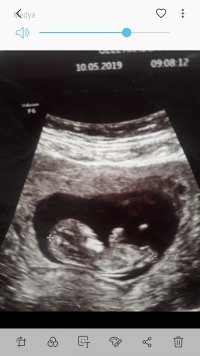

Nub teorisine göre bebeğimin cinsiyetini merak ediyorum. Bebeğim daha 12 haftalık sizce kızmı erkek mi? Tahminlerinizi alabilirmiyim. Teşekkür ediyorum

Nub yanılmıyor pek bebeğiniz kız görünüyor. Rabbim kucağınıza alacağınız o mutlu günü size, sizin gibi bebek bekleyen tüm anne adaylarına nasip etsin Amiiin 🙂 Hayırlı bayramlar dilerim...